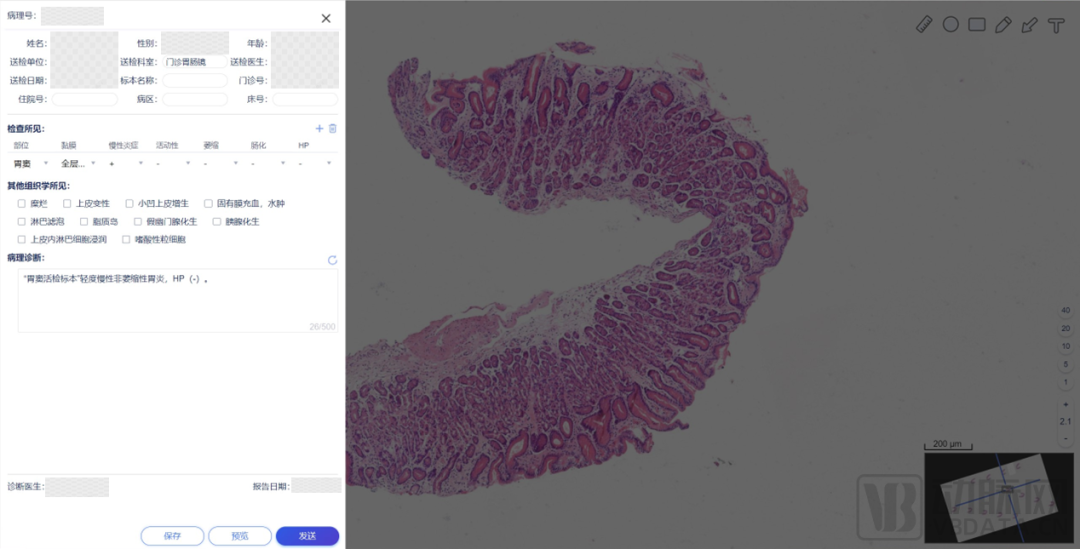

来源:商汤科技